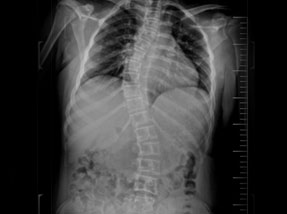

• Pre-Surgery

• Post Surgery

Case 1